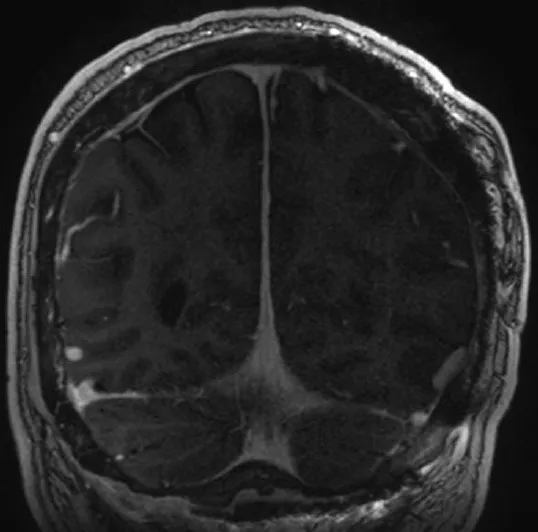

48岁男性患者因头痛加剧伴视物模糊3天就诊。术前影像学检查显示窦汇区存在约11.5厘米的轴外占位性病变,增强扫描呈现明显强化特征。脑血管造影检查证实病变导致上矢状窦、窦汇及左侧横窦近端发生闭塞,皮质静脉通过Labbe静脉实现引流功能,深部引流则依赖枕窦完成。体格检查发现患者存在下方视野偏盲症状,枕后部可触及巨大坚硬隆起,表面皮肤未见异常表现。

术前诊断性检查包括头颅磁共振成像(MRI)及磁共振血管成像(MRA),结果显示直径11.5厘米的肿瘤病灶跨越幕上及幕下区域,向双侧顶叶与枕叶延伸,并侵犯上矢状窦、窦汇及横窦近端。肿瘤经颅骨侵犯至枕部头皮及真皮层。脑血管造影显示上矢状窦、窦汇及横窦近端部分节段血流消失,深部静脉经枕窦引流,皮质静脉经增粗的Labbe静脉引流。